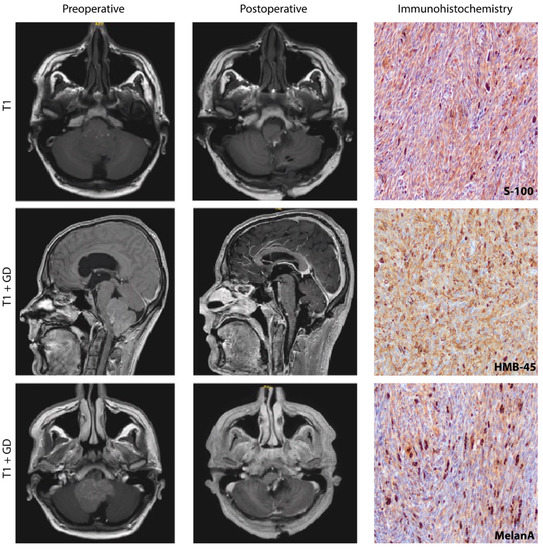

Abstract

1. Introduction